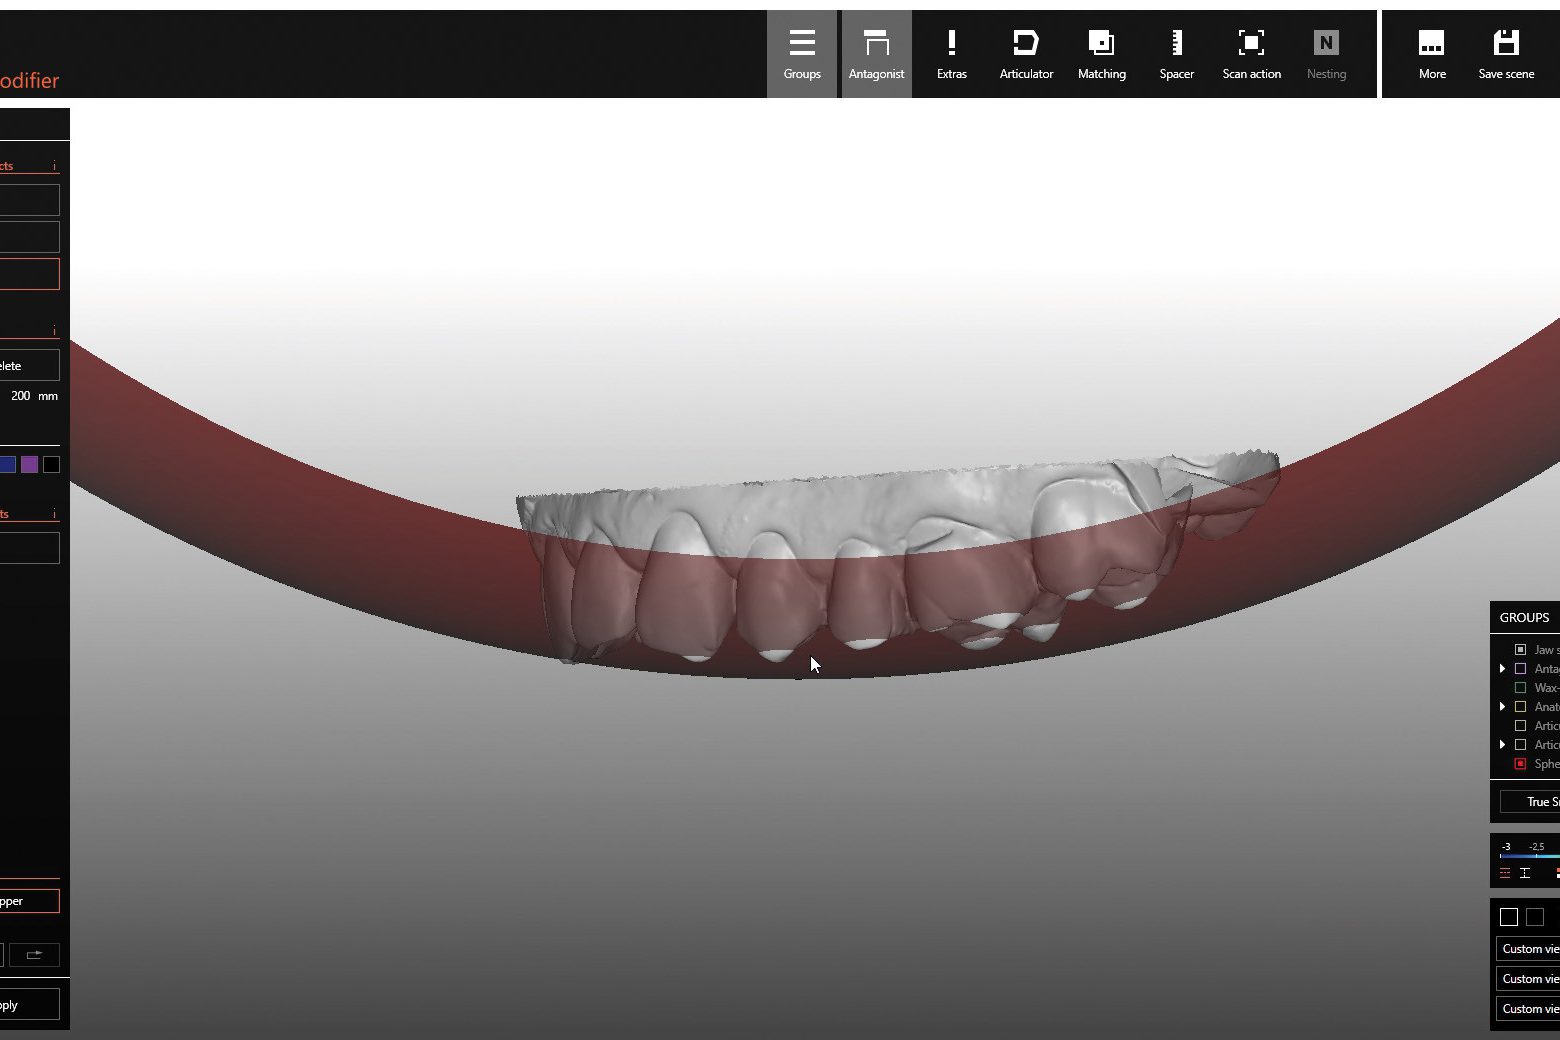

- Digital tooth set-up in the Zirkonzahn.Modifier software using the DEMI tooth set from the Heroes Collection virtual library; tooth individualisation

- Design and milling of a digital block-out model for the upper and lower mock-ups in Temp Premium Flexible

- Based on the patient-specific model articulation and the selection of a digital Monsons Sphere with Ø 240 mm, the areas to be prepared in the occlusal region were highlighted and a preparation guide for the upper jaw was created. After determining the centric relationship, it turned out that, due to the new occlusal height, the canine 23 needed a palatal support surface to optimise function. Therefore, a vestibular and a palatal veneer were designed to avoid too invasive preparation of the natural tooth. During cementation, the vestibular veneer was applied first, and then the palatal one (‘sandwich technique’)